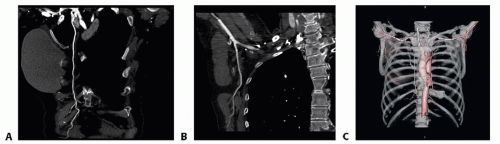

When needed, CT angiography provides detailed information on the vascular anatomy for surgical planning (FIG 3).